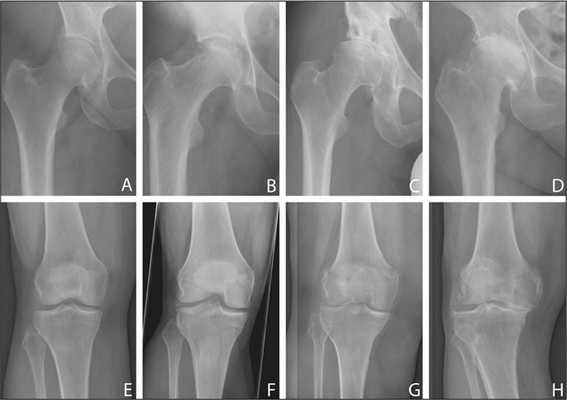

Показания к замене

Посмотрите на рентген, на нем вы видите, до какой степени при запущенном гонартрозе изношен гиалиновый хрящ, обеспечивающий гладкое скольжение суставных поверхностей. Концевые участки костей грубо деформируются нарушая функции сгибания и разгибания конечности вызывая интенсивный болевой синдром.

Динамика болезни на рентгене.

Откладывать хирургию при гонартрозах 3-4 степени чревато деформацией позвоночника. Это происходит из-за хромоты. Дегенеративные процессы артроза глубоко затронут кости, из-за чего они приобретут хрупкость, потеряют плотность и зафиксировать к ним компоненты импланта станет сложно.